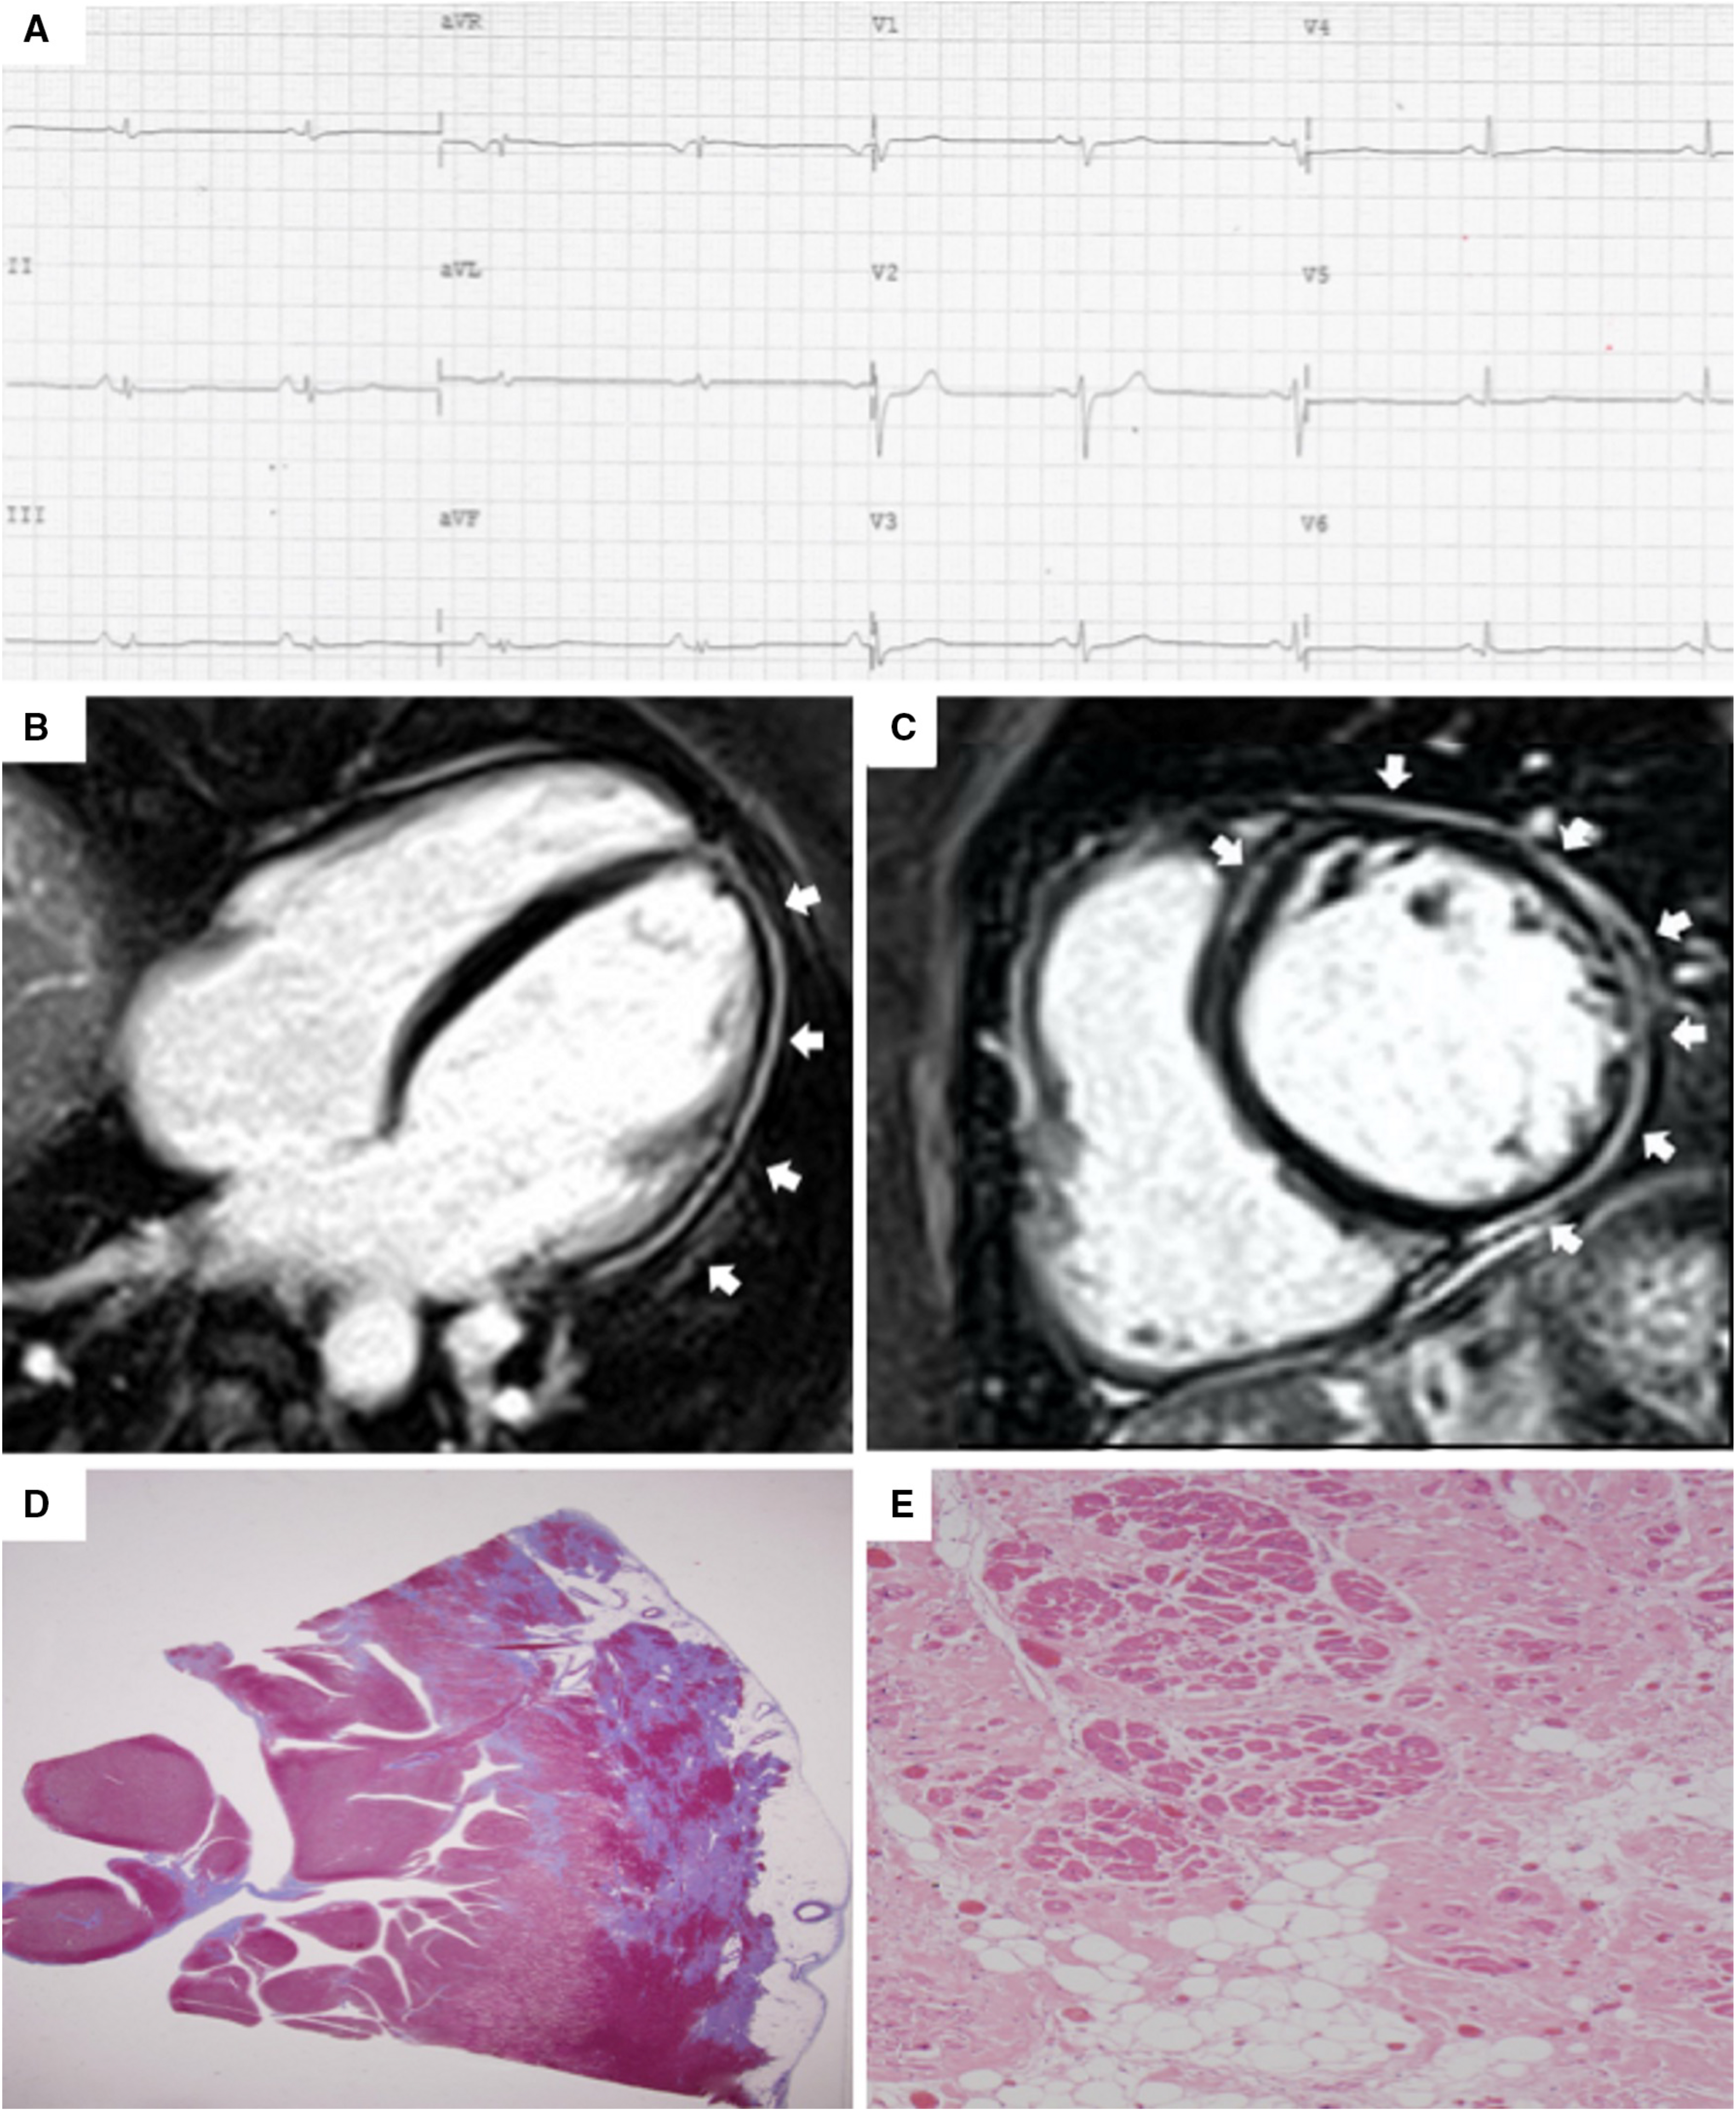

In the early stages of LV involvement, the typical non-ischemic distribution of fibro-fatty replacement sparing the subendocardial layer can explain the absence of wall motion abnormalities, dilatation, or dysfunction of the LV. Thereby, the absence of LV functional abnormalities on echo, cine-CMR or angiography cannot rule out LV involvement, and CE-CMR characterization plays a key role in detection of left-sided ACM [14, 16, 33, 34, 35, 36] (Fig. 4, Ref. [14]).

Fig. 4.Clinical and histopathological features of ALVC. Basal ECG and CMR findings in a patient who underwent cardiac transplantation because of ALVC related to a DSP gene mutation. Basal ECG revealed low QRS voltages in limb leads and flattened T-waves in infero-lateral leads (A). Post-contrast sequences on CMR (four-chamber view, B, and short-axis view, C) revealed subepicardial LGE involving the anterior septum and the whole LV free wall (“ring like” pattern) from basal to apical regions. Histology in LV inferolateral region demonstrated fibrofatty myocardial replacement in the subepicardial layer (D); a magnification of residual myocytes embedded within fibrous and fatty tissue (hematoxylin and eosin stain) (E). The diagnosis was “definite ALVC”. ALVC, arrhythmogenic left ventricular cardiomyopathy; CMR, cardiac magnetic resonance; DSP, desmoplakin gene; LGE, late gadolinium enhancement; LV, left ventricle. Adapted from Cipriani et al. [14].